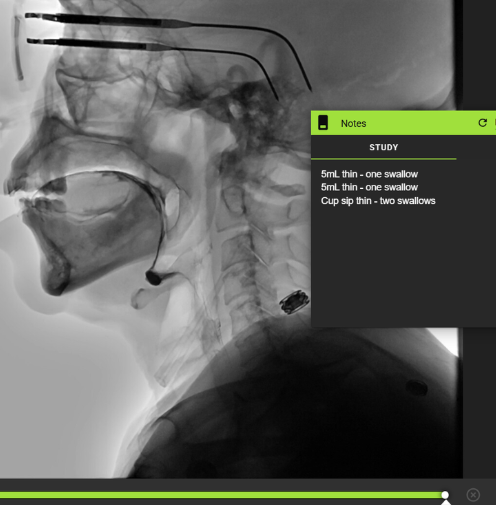

Number of Swallows Per Bolus

Quick Takeaways

Data obtained when completing the ASPEKT-C Method.

When assessing the number of swallows per bolus using the ASPEKT-C Method, a swallow is defined as UES opening plus at least one of the following: pharyngeal constriction, laryngeal elevation and/or hyoid excursion. Do not include swallow attempts.

Steps for Completion

Use frame-by-frame review with audio on to determine bolus administration.

Track the number of swallows per bolus.

Example: Patient swallowed twice with cup sip thin independently. Data obtained with frame-by-frame review and detailed using the Notes tool.